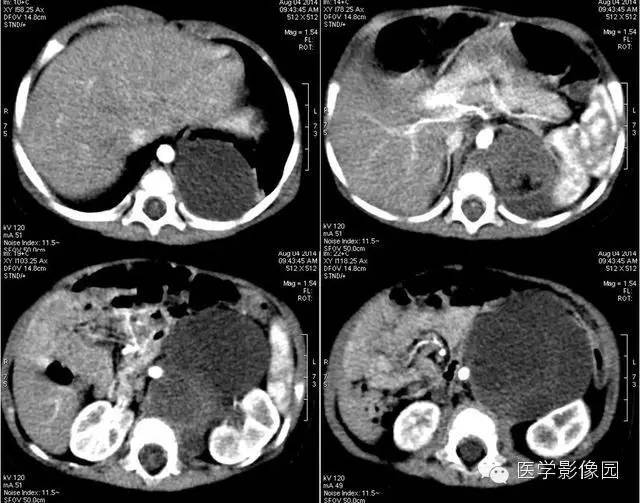

2——增强

3——增强

畸胎瘤是由两个或三个原始胚层组织演化而来的胚胎性肿瘤,大体上囊性、实性或囊实性兼有。囊性畸胎瘤又称皮样囊肿,仅含表皮及其附属成分,基本上均为良性。实性畸胎瘤含有三个胚层成分。按组织学分类可分为良性畸胎瘤和恶性畸胎瘤。良性畸胎瘤由分化良好的成熟组织构成,故又称为成熟畸胎瘤,瘤体囊性部分多于实质部分,小儿中绝大部分均为良性畸胎瘤。恶性畸胎瘤由胚胎发生时期的未成熟组织构成,实质部分常多于囊性部分,恶性畸胎瘤在小儿中十分少见。小儿畸胎瘤以女性多见,男女之比约为1:3-4,腹部包块和腹胀为腹膜后畸胎瘤主要的临床表现,患儿一般状况良好。

恶性畸胎瘤瘤体以实体为主,病变边界模糊不清,可侵犯周围组织,肿块大小对鉴别良恶性意义不大。